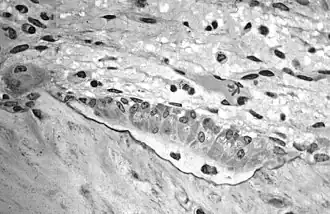

-

Light micrograph of an osteoclast displaying typical distinguishing characteristics: a large cell with multiple nuclei and a "foamy" cytosol.

Light micrograph of an osteoclast displaying typical distinguishing characteristics: a large cell with multiple nuclei and a "foamy" cytosol. -

Light micrograph of osteoblasts, several displaying a prominent Golgi apparatus, actively synthesizing osteoid containing two osteocytes.

Light micrograph of osteoblasts, several displaying a prominent Golgi apparatus, actively synthesizing osteoid containing two osteocytes. -